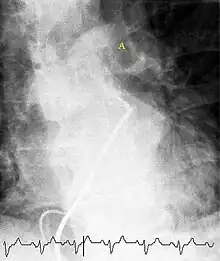

Fluoroscopic pulmonary angiography

Selective pulmonary angiogram revealing clot (labeled A) causing a central obstruction in the left main pulmonary artery. ECG tracing shown at the bottom.

Historically, the gold standard for diagnosis was pulmonary angiography by fluoroscopy, but this has fallen into disuse with the increased availability of non-invasive techniques that offer similar diagnostic accuracy.[69]